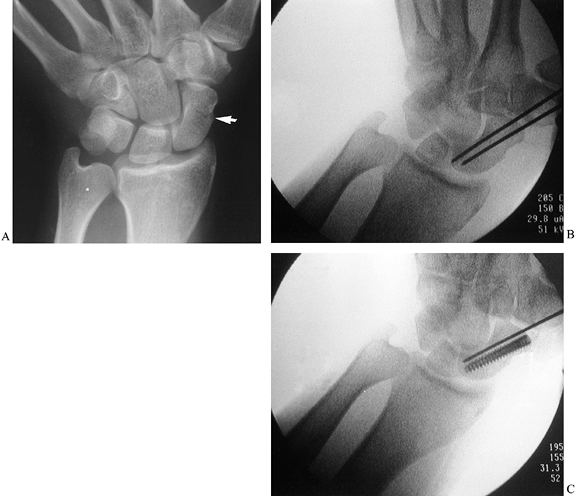

![]() |

Figure 42.8. A nondisplaced scaphoid fracture (arrow) in a 40-year-old physician. The fracture healed in 2 months following insertion of an Acutrak headless, cannulated screw.

Under direct radiographic imaging, drill a pin down the axis of the bone (Fig. 42.8B, arrow).

Insert a second pin parallel to the first to prevent rotation and possible displacement of the fracture.

Drill an Acutrak cannulated screw over the first wire; then, remove the second wire (Fig. 42.8C).